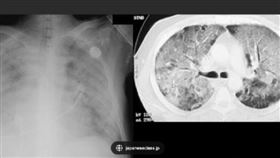

中國一堆「大白肺」 病毒學專家5個解釋

中國COVID-19疫情炸鍋之後,頻傳重症「大白肺」...